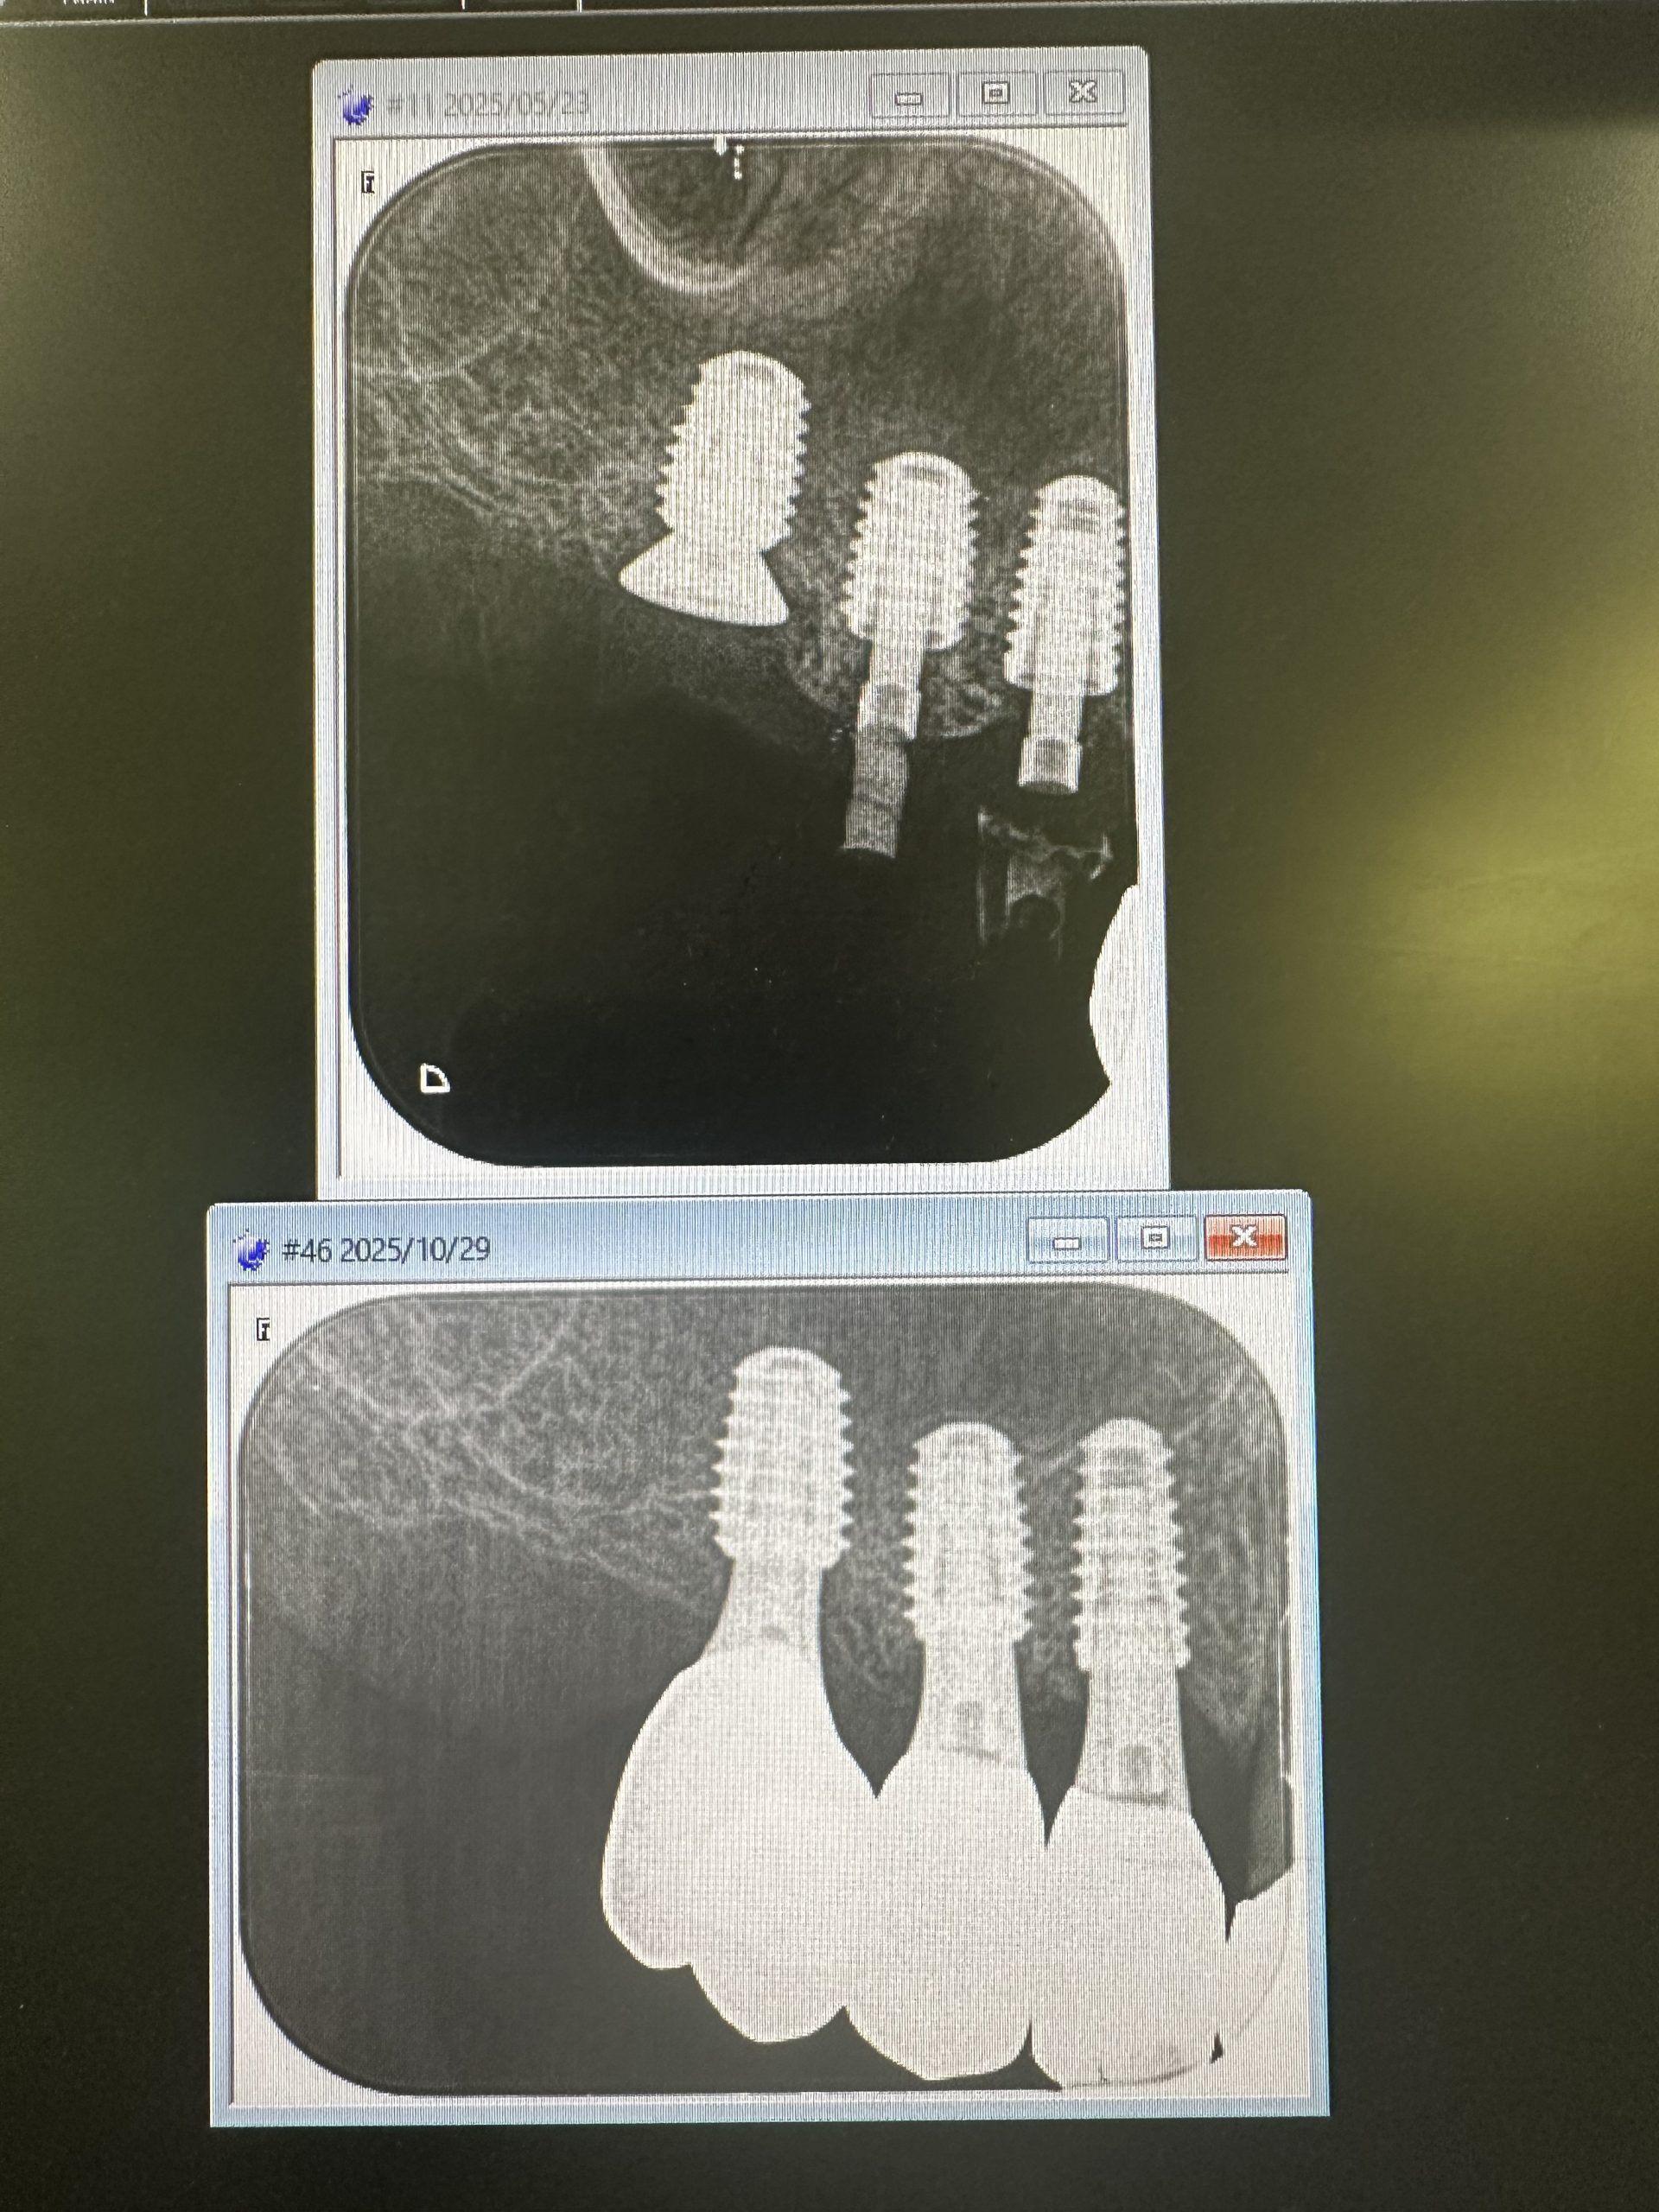

今年5月オペ、6番は残存骨2から3ミリ程度での、ソケットリフトデンサーバーによるリフト

4.5番は6wで仮歯装着、しかし6番は5ヶ月近くかかったが、本日最終補綴物セット

昼からは前歯抜歯即時、ソケットシールド、即時荷重まで 切開無し